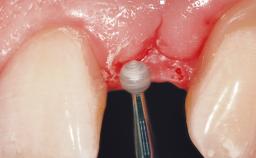

Immediate Flapless Placement of an Implant in a Maxillary Left Central Incisor Site

A 29-year-old female patient presented for treatment to replace the upper left central incisor tooth with an implant- supported restoration. The tooth had been intermittently symptomatic for the previous 12 months. The tooth had originally suffered trauma about 15 years previously. Several endodontic treatments had been performed, including an apicectomy procedure to retain the tooth. The patient was healthy and a non-smoker. She had reasonable expectations in regard to esthetic outcomes and the risk of marginal tissue recession following treatment. At medium smile, the gingival margins of the upper teeth were visible, with a display of 3 to 4 mm of the gingival margins. Gingival recession of tooth 21 and a discrepancy in the gingival levels between teeth 11 and 21 was observable during normal speech and smile.

Placement Protocol Immediate implant placement

Tooth Site Maxillary incisor or canine

Socket Morphology Single-root socket

Socket Integrity Damage to one or more bone walls